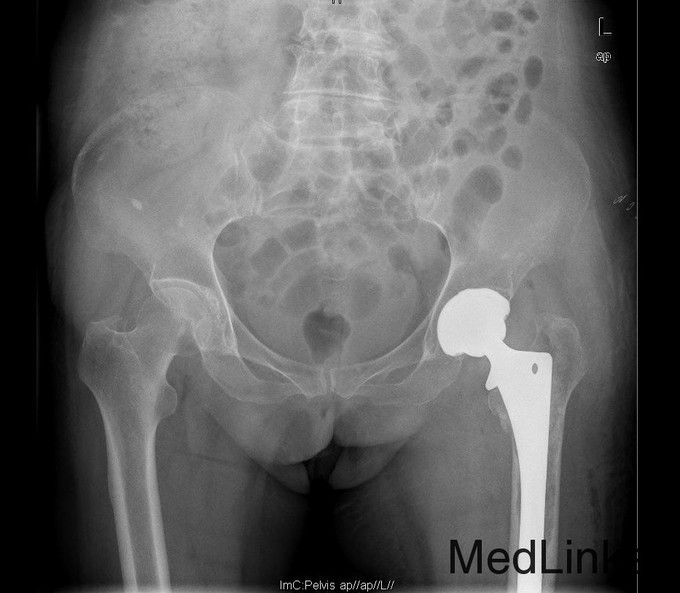

查体:专科:左髋部后外侧陈旧手术瘢痕,左髋关节前方压痛、无轴向叩击痛阴性,无大转子叩击痛,双下肢感觉及血运均正常。双下肢肌力V级。动量:右髋内外旋诱发疼痛,屈曲90度疼痛。外旋明显滚动试验阴性,左髋4字试验阳性。双下肢等长。左髋关节屈90°,伸0°,外展40°,内收20°,内旋30°外旋10°。右髋关节屈120°,伸直0°,外展40°,内收20°,内旋30°外旋30°。 辅助检查:2010-12-08 ESR 6.0mm/h,2011-01-04外院CRP8.5mg/l(参考范围0-10mg/l)X线示左双动股骨头置换术后,假体松动、下沉,髓腔内可见骨水泥影。近端干骺端骨质明显缺损。髓腔内侧皮质形态不规则。

诊断:左双动股骨头置换术后假体松动、下沉、股骨骨缺损(PaproskyII型) 治疗:患者在全麻下左双动股骨头假体取出+同种异体骨植骨+左全髋关节翻修术,术后予以抗炎(二联)+抗凝+镇痛+护胃+补液等治疗,并予以抗骨质疏松药物